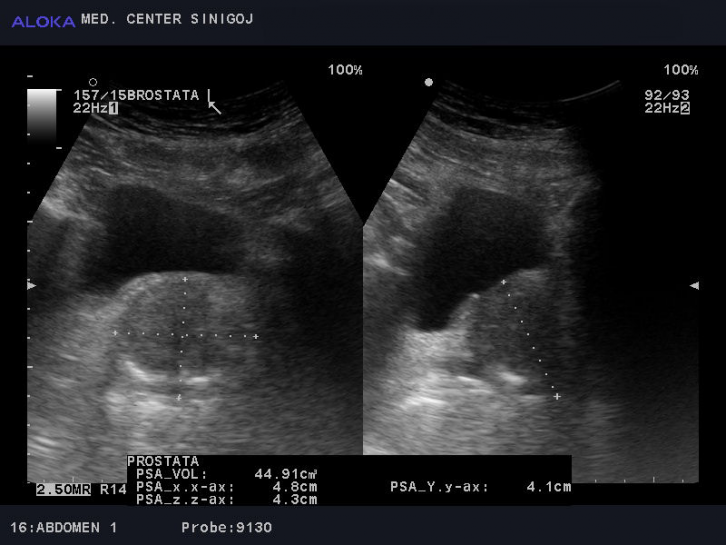

Ultrazvok prostate - benigna hipertrofija prostate

Benigna hipertrofija prostate (BHP)

Pri moških po 50 letu prihaja do hormonskih sprememb in do povečanja prostate. Povečana prostata otežuje praznjenje mehurja in posledično prihaja do zastoja urina v mehurju.

Kaj zajema preventivni pregled prostate: klinični pregled prostate, ultrazvok prostate in mehurja.

Z ultrazvokom ocenimo:

- velikost in strukturo prostate

- velikost, lumen in steno mehurja

- volumen zaostalega urina v sečnem mehurju pred in po mikciji

Določanje PSA v krvi

Določanje vrednosti s-PSA je standardna preiskava pri sumu na bolezen prostate. Vrednost psa uporabljamo v razlikovanju med benignimi in malignimi spremembami prostate.